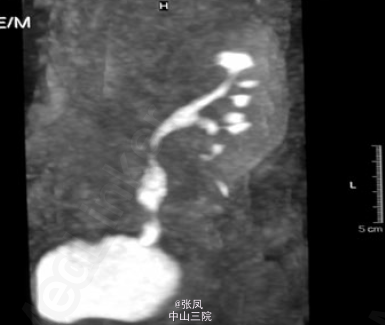

患者术后第12天造影检查提示移植肾输尿管中段部位轻微狭窄,术后20天再次造影检查提示移植肾输尿管明显狭窄并坏死。

患者男,28岁,2009年因头晕、乏力到当地医院就诊,检测发现血肌酐超过1000umol/L,诊断为尿毒症,并开始规律血液透析治疗。2014年在我院行异体肾移植术,手术过程顺利,术中发现移植肾输尿管血供稍差,术后尿量约300ml/h,术后一周后肌酐降至正常,为112umol/L。术后第9天出现尿量减少,约1000ml/d,肌酐升高至145umol/L,考虑排斥反应,给予激素冲击治疗后无明显效果,术后第12天患者出现移植肾周疼痛,压痛明显,为排除尿瘘,行移植肾造影发现移植肾输尿管中段部位轻微狭窄,考虑输尿管狭窄合并少量尿瘘,暂行保守治疗。术后20天移植肾周疼痛加重,并体温升高,无尿,典型的尿瘘症状,再次造影检查提示移植肾输尿管坏死,行紧急手术治疗。